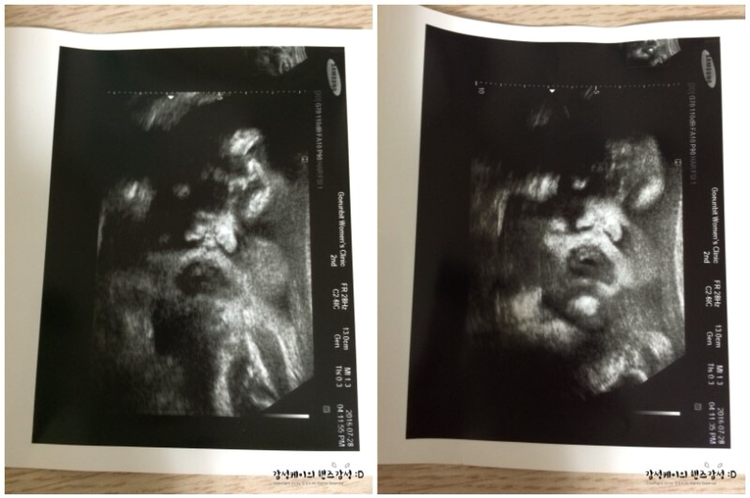

두근두근 검사시간. 기계가 나의 배에서 움직일 때마다 조금씩 보이는 아이의 모습. 또 배가 고픈 건지 양수를 먹고 있는 건지 아이는 오늘도 입을 오물오물 거리고 있다. 그런데 일주일 전보다 아기의 체중이 늘었다! 26.8킬로!! 열심히 과일을 먹은 보람이 있었나 보다. 선생님께서도 확실히 저번보다 아기배가 커졌다고 말해주셨다. 이대로 가면 문제없겠다고 하시면서 말이다. 37주. 솔직히 내가 8개월 만에 태어나고 또 언니가 38주에 아기를 낳을걸 생각한다면 지금 아기를 낳아도 조산이 아닌 시기이다. 그래서인지 내 마음이 더 두근두근 거리는것 같다.